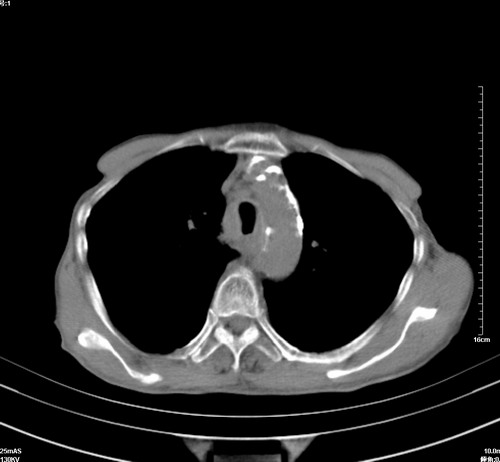

病人,女,79岁,主要因腹疼二月入院,彩超,肝,胆,脾,未见异常,胸透上消化道造影未见异常,化验白细胞增高,内科医生让做胸部ct检查,因为熟人多做了腹部(外科会诊考虑胆囊炎).现ct片如下请假各位战友.

中后纵隔占位,气管、食道受压、变形、移位。恶性可能性大。

考虑:中后纵隔转移瘤可能性大,主动脉硬化。

1 气管旁、隆突下淋巴结明显肿大,肝左叶外侧段低密影,都考虑转移。

后中纵隔团块影,伴气管、食道受压移位,首先考虑转移瘤,肝s5段低密度灶。建议增强检查,另外其结肠是否有问题请提供,右肺部分肺叶局限含气增多,考虑局限肺气肿。

建议强化检查,考虑纵隔型肺癌,小细胞可能性大。